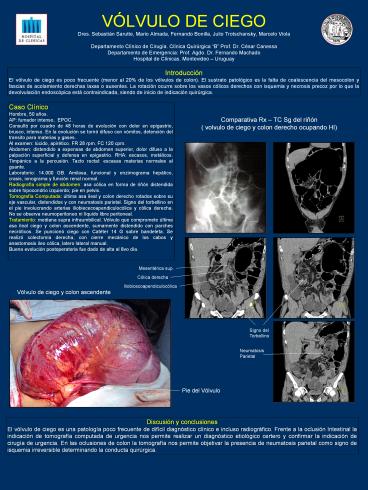

Comparativa Rx TC Sg del riñón ( volvulo de

ciego y colon derecho ocupando HI)

Mesentérica sup.

Cólica derecha

Iliobicecoapendiculocólica

Vólvulo de ciego y colon ascendente

Signo del Torbellino

Neumatosis Parietal

Pie del Vólvulo